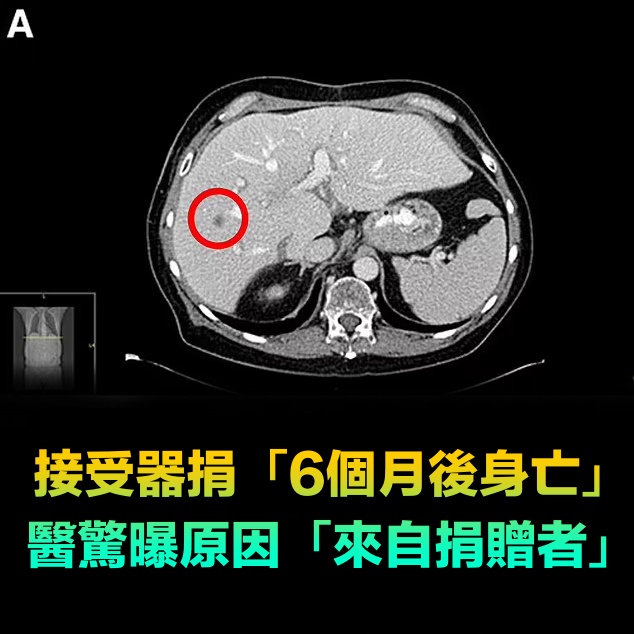

接受器捐「6個月後身亡」!醫驚曝原因「來自捐贈者」

根據《經濟日報》報導,北醫附醫器官勸募暨移植中心主任江仰仁說明,若移植器官內存在小於1公分、甚至更微小的腫瘤,受限於現有檢驗技術的極限值,「確實很難被發現」。他強調,此案例屬於「極度罕見的特殊狀況」,台灣至今尚未發生過類似案例。

不過江仰仁回憶,2019年前後,台灣某醫學中心的移植團隊在協助移植肺臟時,術前檢查一切正常,但當肺臟摘除後,醫師憑藉肉眼觀察,意外發現肺臟表層有個不到1公分的微小結節。為求謹慎,醫療團隊立即將組織送往病理科進行切片檢查,結果證實該結節為惡性腫瘤。在確認診斷後,醫療團隊當機立斷,馬上取消這次肺臟移植手術,避免了潛在的癌症傳播風險,也凸顯器官移植篩檢面臨的實際困難與挑戰。